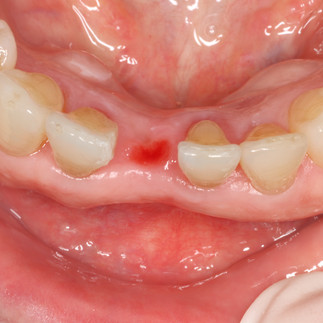

Before Surgery

Pre-operative observation : Missing tooth #41